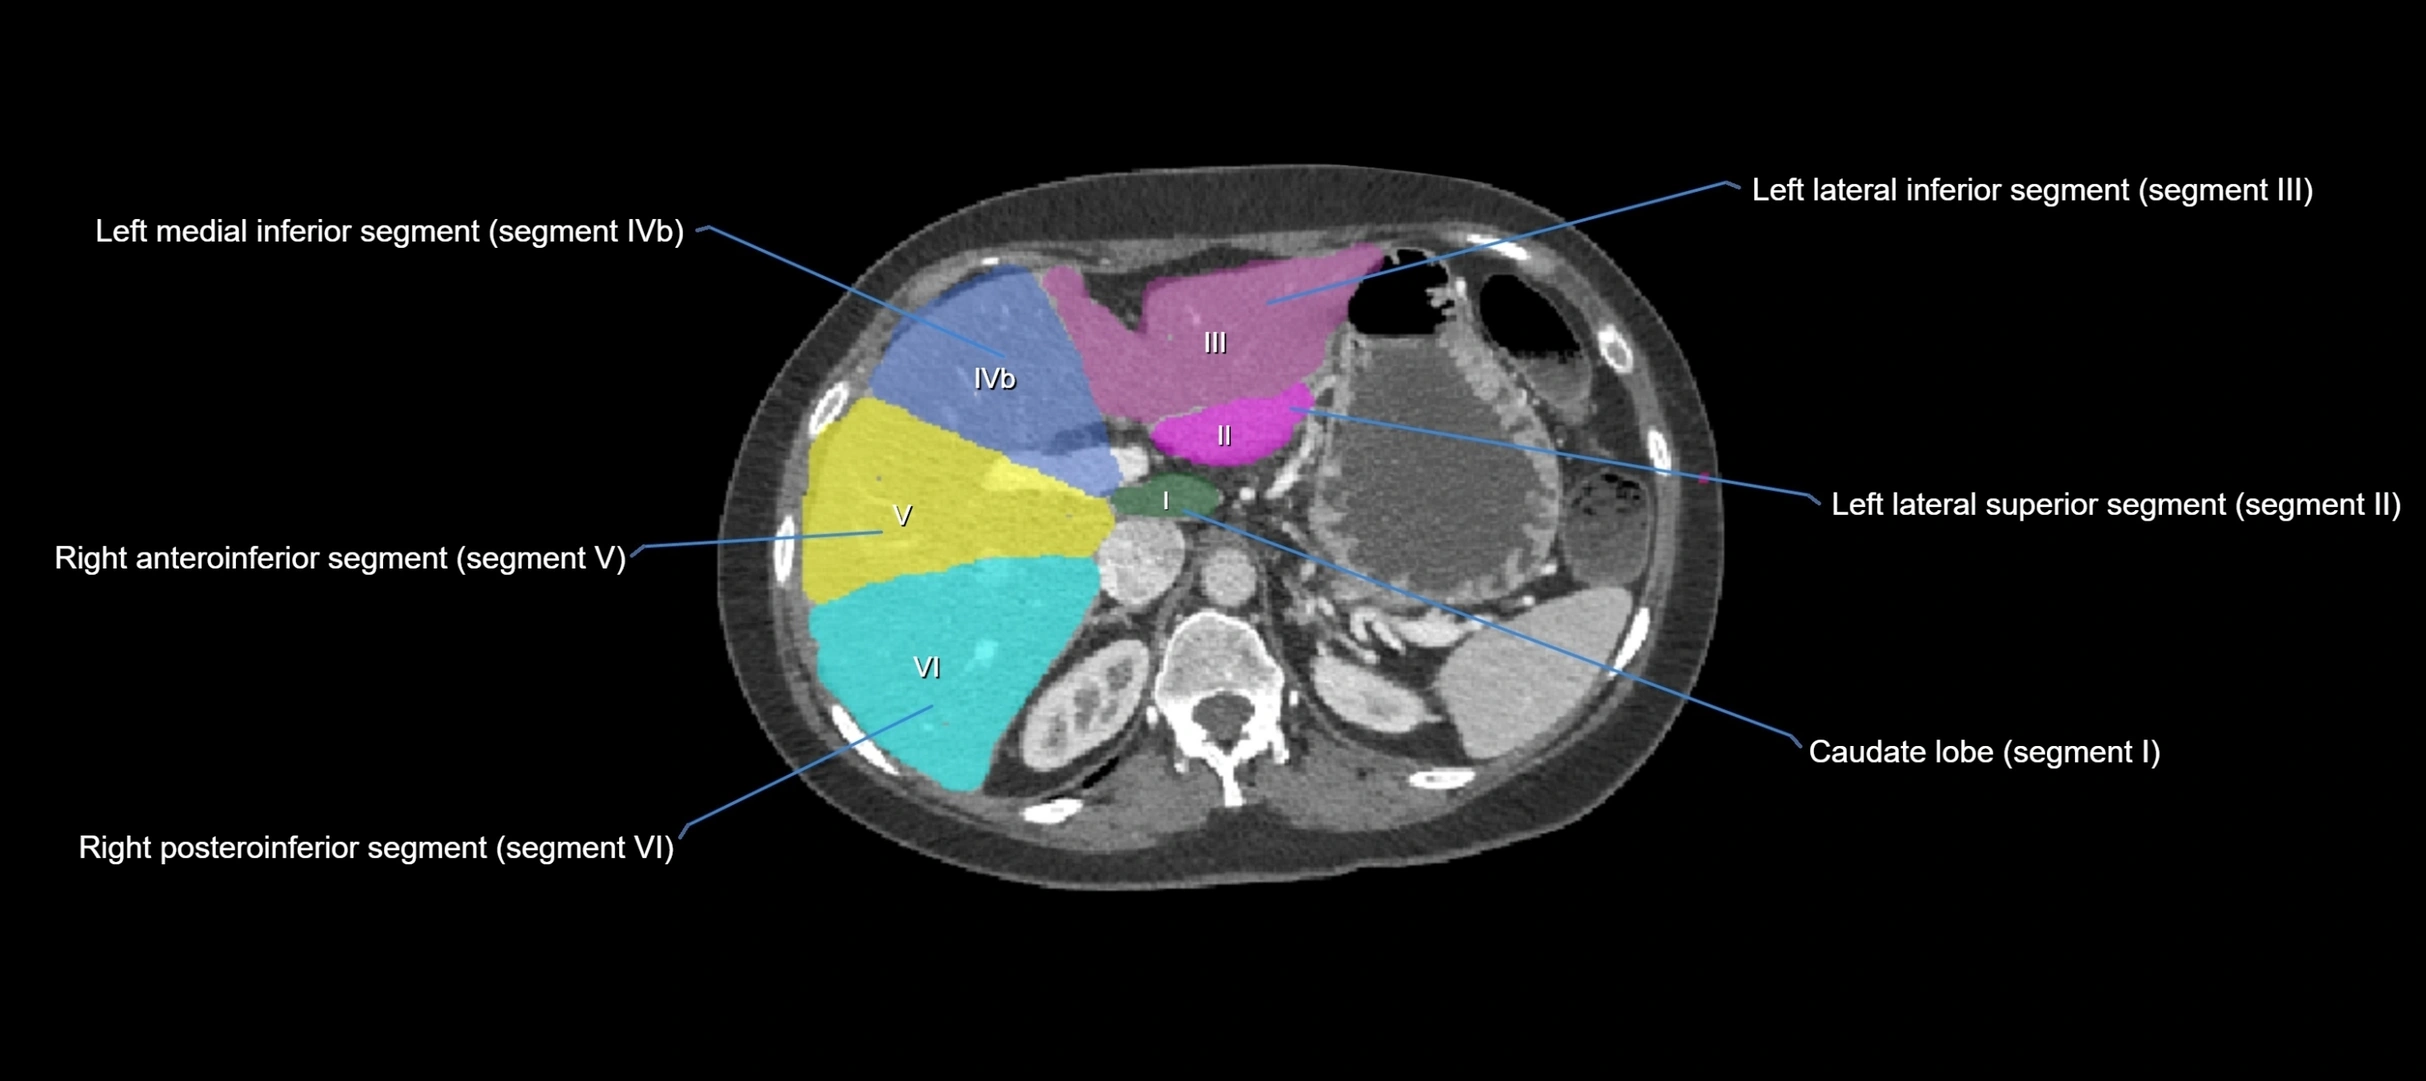

The caudate lobe of the liver is a distinct anatomical subdivision of the liver, designated as segment I in Couinaud’s classification. It lies on the posterior surface of the liver, between the fissure for the ligamentum venosum (left boundary) and the groove for the inferior vena cava (IVC) (right boundary). Superiorly, it is related to the posterior liver surface, and inferiorly it is separated from the left lobe by the porta hepatis.

• Segment I (Couinaud classification)